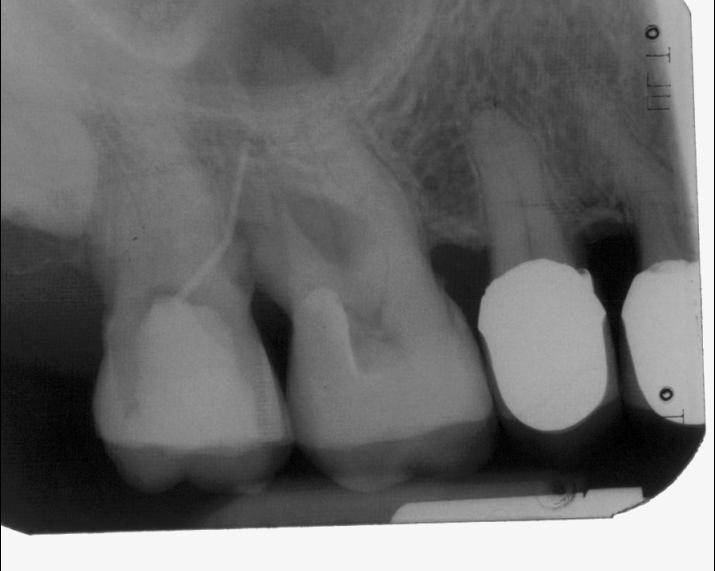

Röntgenologischer Ausgangsbefund im Febr. 2003 mit caries profunda, starken Krümmungen sowohl der mesiobuccalen wie auch der distobuccalen Wurzeln

Zustand unmittelbar vor Behandlungsbeginn im Juni 2003. Die Fraktur des distalen Zahnanteils hat die Patientin jetzt zur Einwilligung in die Behandlung motiviert. Auffällig ist in dieser Projektion die besonders starke Krümmung der mb Wurzel sowie die knochennahe Defektlage distal. Es erfolgte zunächst die Kariesentfernung gefolgt von einer chirurgischen Kronenverlängerung zur Herstellung der biologischen Breite sowie Ermöglichung des sog. Ferrule-Effektes. Danach wurde der Zahn adhäsiv aufgebaut. Erst jetzt wurde mit der eigentlichen WKB begonnen